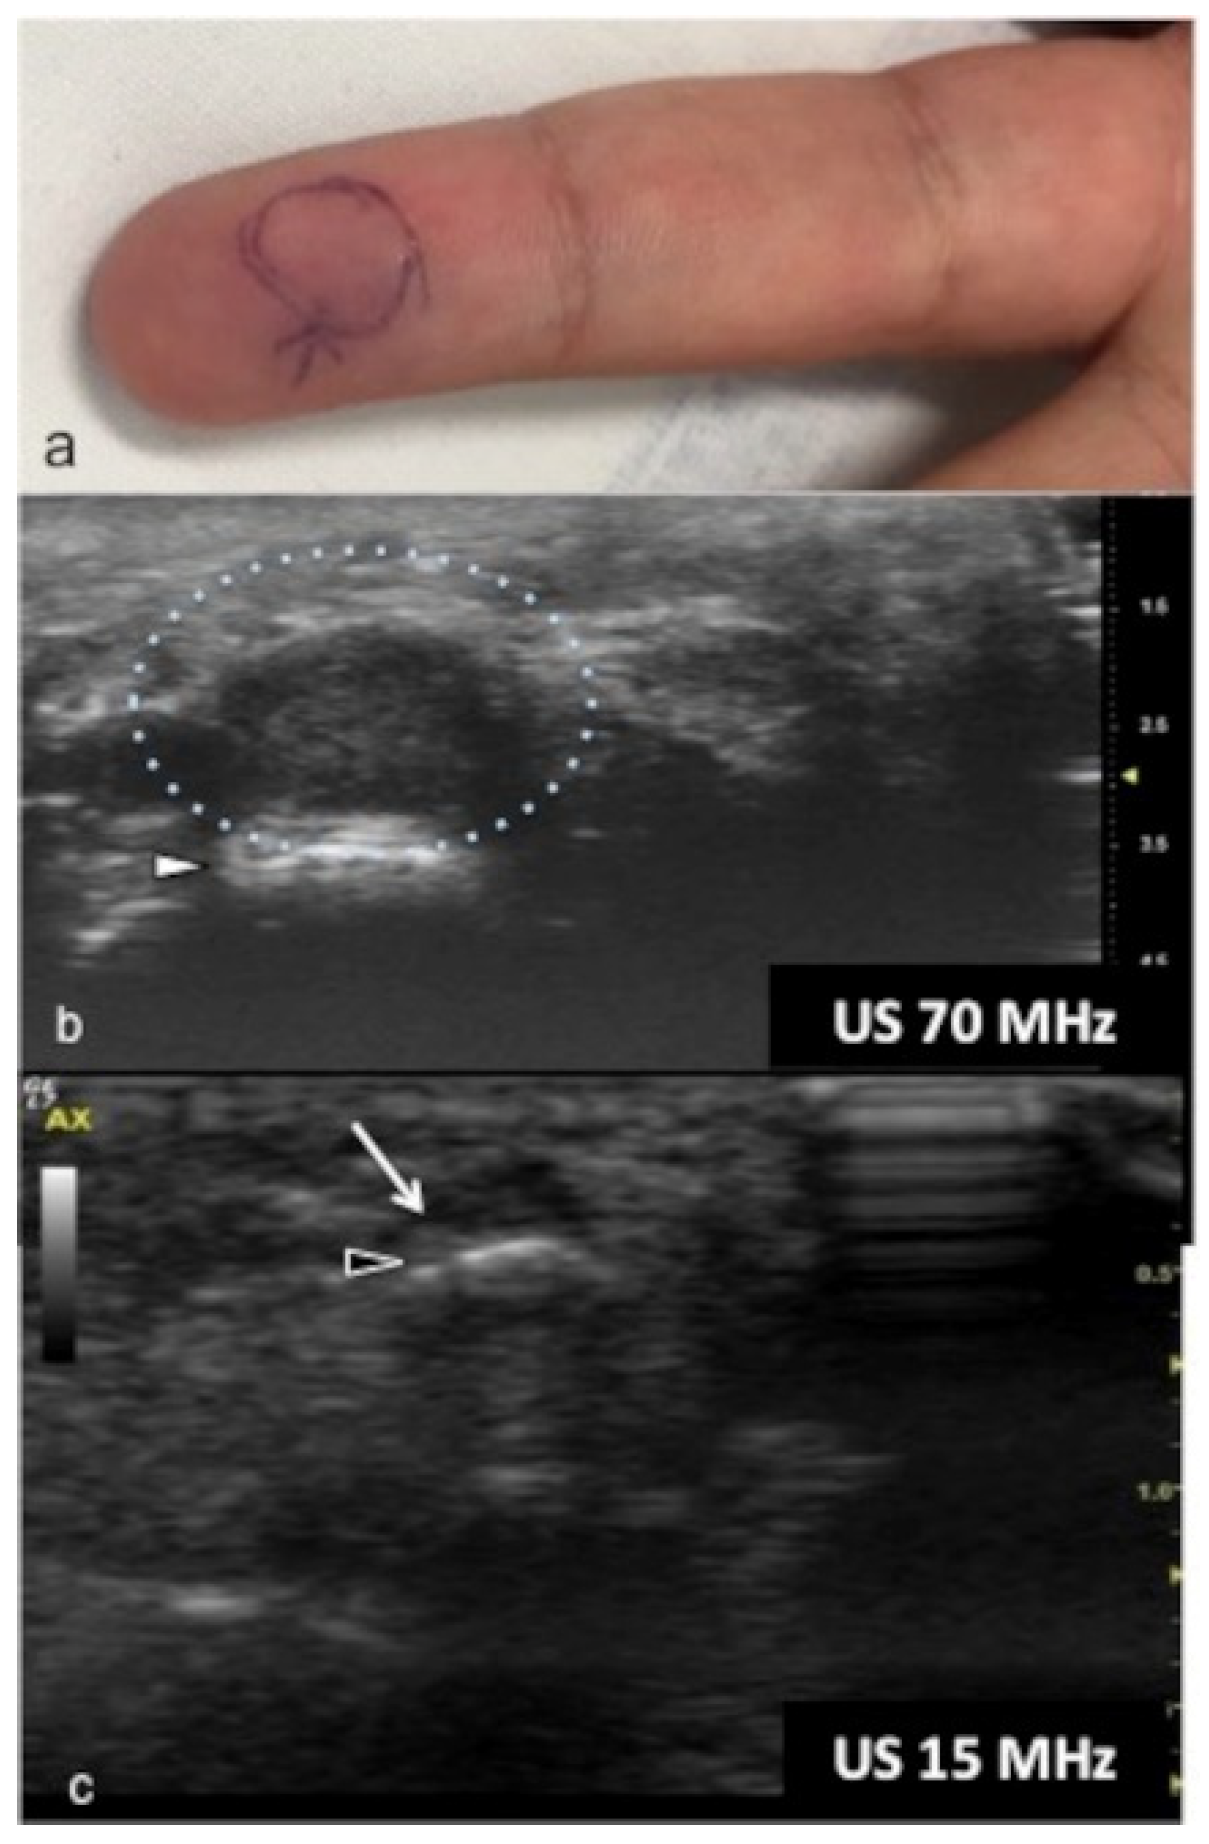

UHFUS could represent an advantageous technique for the identification of small and soft-tissue neoformations such as glomus tumors (Figure 11 and Figure 12).

Figure 11.

Glomus tumor. The location corresponds to the pulp of finger IV (a). The patient had the classical triad of symptoms: paroxysmal pain, pinpoint pain, and cold hypersensitivity, lasting for two years. In (b), UHFUS shows a well-delimited nodule in contact with the adjacent phalangeal bone (arrowhead), but no cortical deformity is present. No significant hyperemia on color Doppler was noticed. On CUS (c), the nodule was delineated only thanks to the help of the preliminary UHFUS exam.

Glomus tumors are rare, benign, vascular neoplasms arising from the glomus body, which is a contractile neuromyoarterial structure found in the reticular dermis. This structure controls blood pressure and temperature by regulating blood flow in the cutaneous vasculature. Hyperplasia in any of these parts can lead to tumor formation, which is extremely painful. Glomus tumors account for 1–5% of soft-tissue tumors of the hand, and 75% of them are subungual in location. Other less commonly involved sites in the hand are the nail matrix, nail bed, and pulp of the finger. The delay in diagnosing these tumors for many years is a significant problem. It is not uncommon that patients are easily misdiagnosed with conditions such as neuropathic complaints, arthritis, or neuralgia and undergo unsuitable treatment. For these reasons, when the clinical examination is equivocal, noninvasive imaging techniques may be needed to aid in the diagnosis and delineate the anatomy preoperatively. Complete surgical excision of the tumor is the only effective treatment. Incomplete excision is considered the main cause of recurrence. US follow-up and/or intraoperative US may be useful for reducing recurrence and ensuring adequate resection, and the UHFUS tool is promising in this field [56].